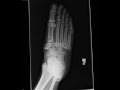

Lisfranc Fracture Dislocation

This is a patient who presents with foot pain following a motor vehicle accident. Frontal, oblique, and lateral radiographs of the foot were obtained. The frontal radiograph demonstrates abnormal alignment of the foot with the red arrow representing a widened interspace between the first and second metatarsals. Additionally, the medial margin of the intermediate cuneiform should always be aligned with the medial margin of the second metatarsal base. In this case, the second through fifth metatarsals are dislocated medially. Additionally, the green arrow demonstrates offset of the medial cuneiform and the base of the hallux metatarsal second to medial dislocation. These findings are also nicely demonstrated on the second radiograph. The lateral radiograph demonstrates dorsal dislocation of the second and third metatarsals relative to the midfoot and hindfoot. This is demonstrated by the red arrow. These findings are consistent with a Lisfranc fracture dislocation. These is a serious injury that usually occurs in the setting of high energy trauma or diabetes. Dislocation is usually secondary to disruption of the Lisfranc ligament as well as the intermetarsal ligaments. Fractures of the bases of the metatarsal as well as cuneiform bones are commonly seen. Treatment is surgical.